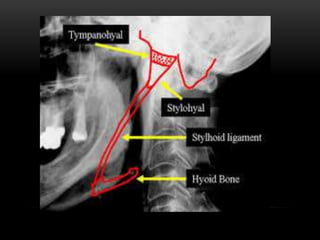

OSSIFICATION OF THE STYLOID LIGAMENT

• Normal length of styloid process- 25mm

• Ossification of the styloid ligament usually extends downwards

from the base of the skull and commonly occurs bilaterally.

• In rare cases the ossification begins at the lesser horn of the hyoid

or in the central area of the ligament. The associated conditions

are Eagle's Syndrome, Styloid Syndrome and Styloid Chain

Ossification.

RADIOGRAPHIC FEATURES

In the panoramic image it is seen as a linear, long, tapering, thin, radiopaque

process that is thicker at its base, extending forward from the region of the

mastoid process and crosses the posteroinferior aspect of the ramus towards the

hyoid bone. The hyoid bone is positioned approximately parallel to or

superimposed on the posterior aspect of the inferior cortex of the mandible.